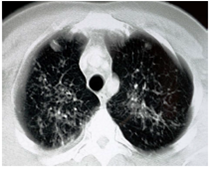

Dos semanas después, el paciente presentó una recaída clínica (figura 1) caracterizada por astenia, adinamia, hiporexia, fiebre intermitente, diaforesisnocturna y tos productiva, por lo cual acudió a urgencias donde se lo encontró en condiciones generales regulares, deshidratado, disneico, taquicárdico e hipotenso. Este cuadro clínico se interpretó como sepsis de posible origen respiratorio. En la tomografía computadorizada (TC) de tórax se observaron opacidades retículo-nodulares gruesas en ambos campos pulmonares. Tras 16 días de hospitalización bajo tratamiento antibiótico con amikacina y piperacilina-tazobactam, el paciente egresó con resolución del cuadro clínico y se le suspendió el infliximab.

En la radiografía de tórax se apreciaron opacidades retículo-nodulares en ambos campos pulmonares (figura 2), hallazgos confirmados por TC (figura 3). La baciloscopia seriada de esputo fue negativa para bacilos ácido-alcohol resistentes (BAAR), y en la colonoscopia y la ileoscopia practicadas se encontró ileítis, una tumoración ulcerada junto a la válvula íleocecal y una lesión ulcerada en el recto distal (figura 4 A y B). Se tomaron, entonces, biopsias de recto, colon e íleon cuyo estudio histopatológico informóun proceso inflamatorio granulomatoso crónico constituido por granulomas poco estructurados en todas las muestras evaluadas. Con la coloración de Ziehl-Neelsen (ZN) se demos-traron BAAR en todas las muestras (figura 5 A y B). Debido a estos hallazgos, se inició inmediatamente el tratamiento antituberculoso, además de la administración de mesalazina (4.000 mg al día).